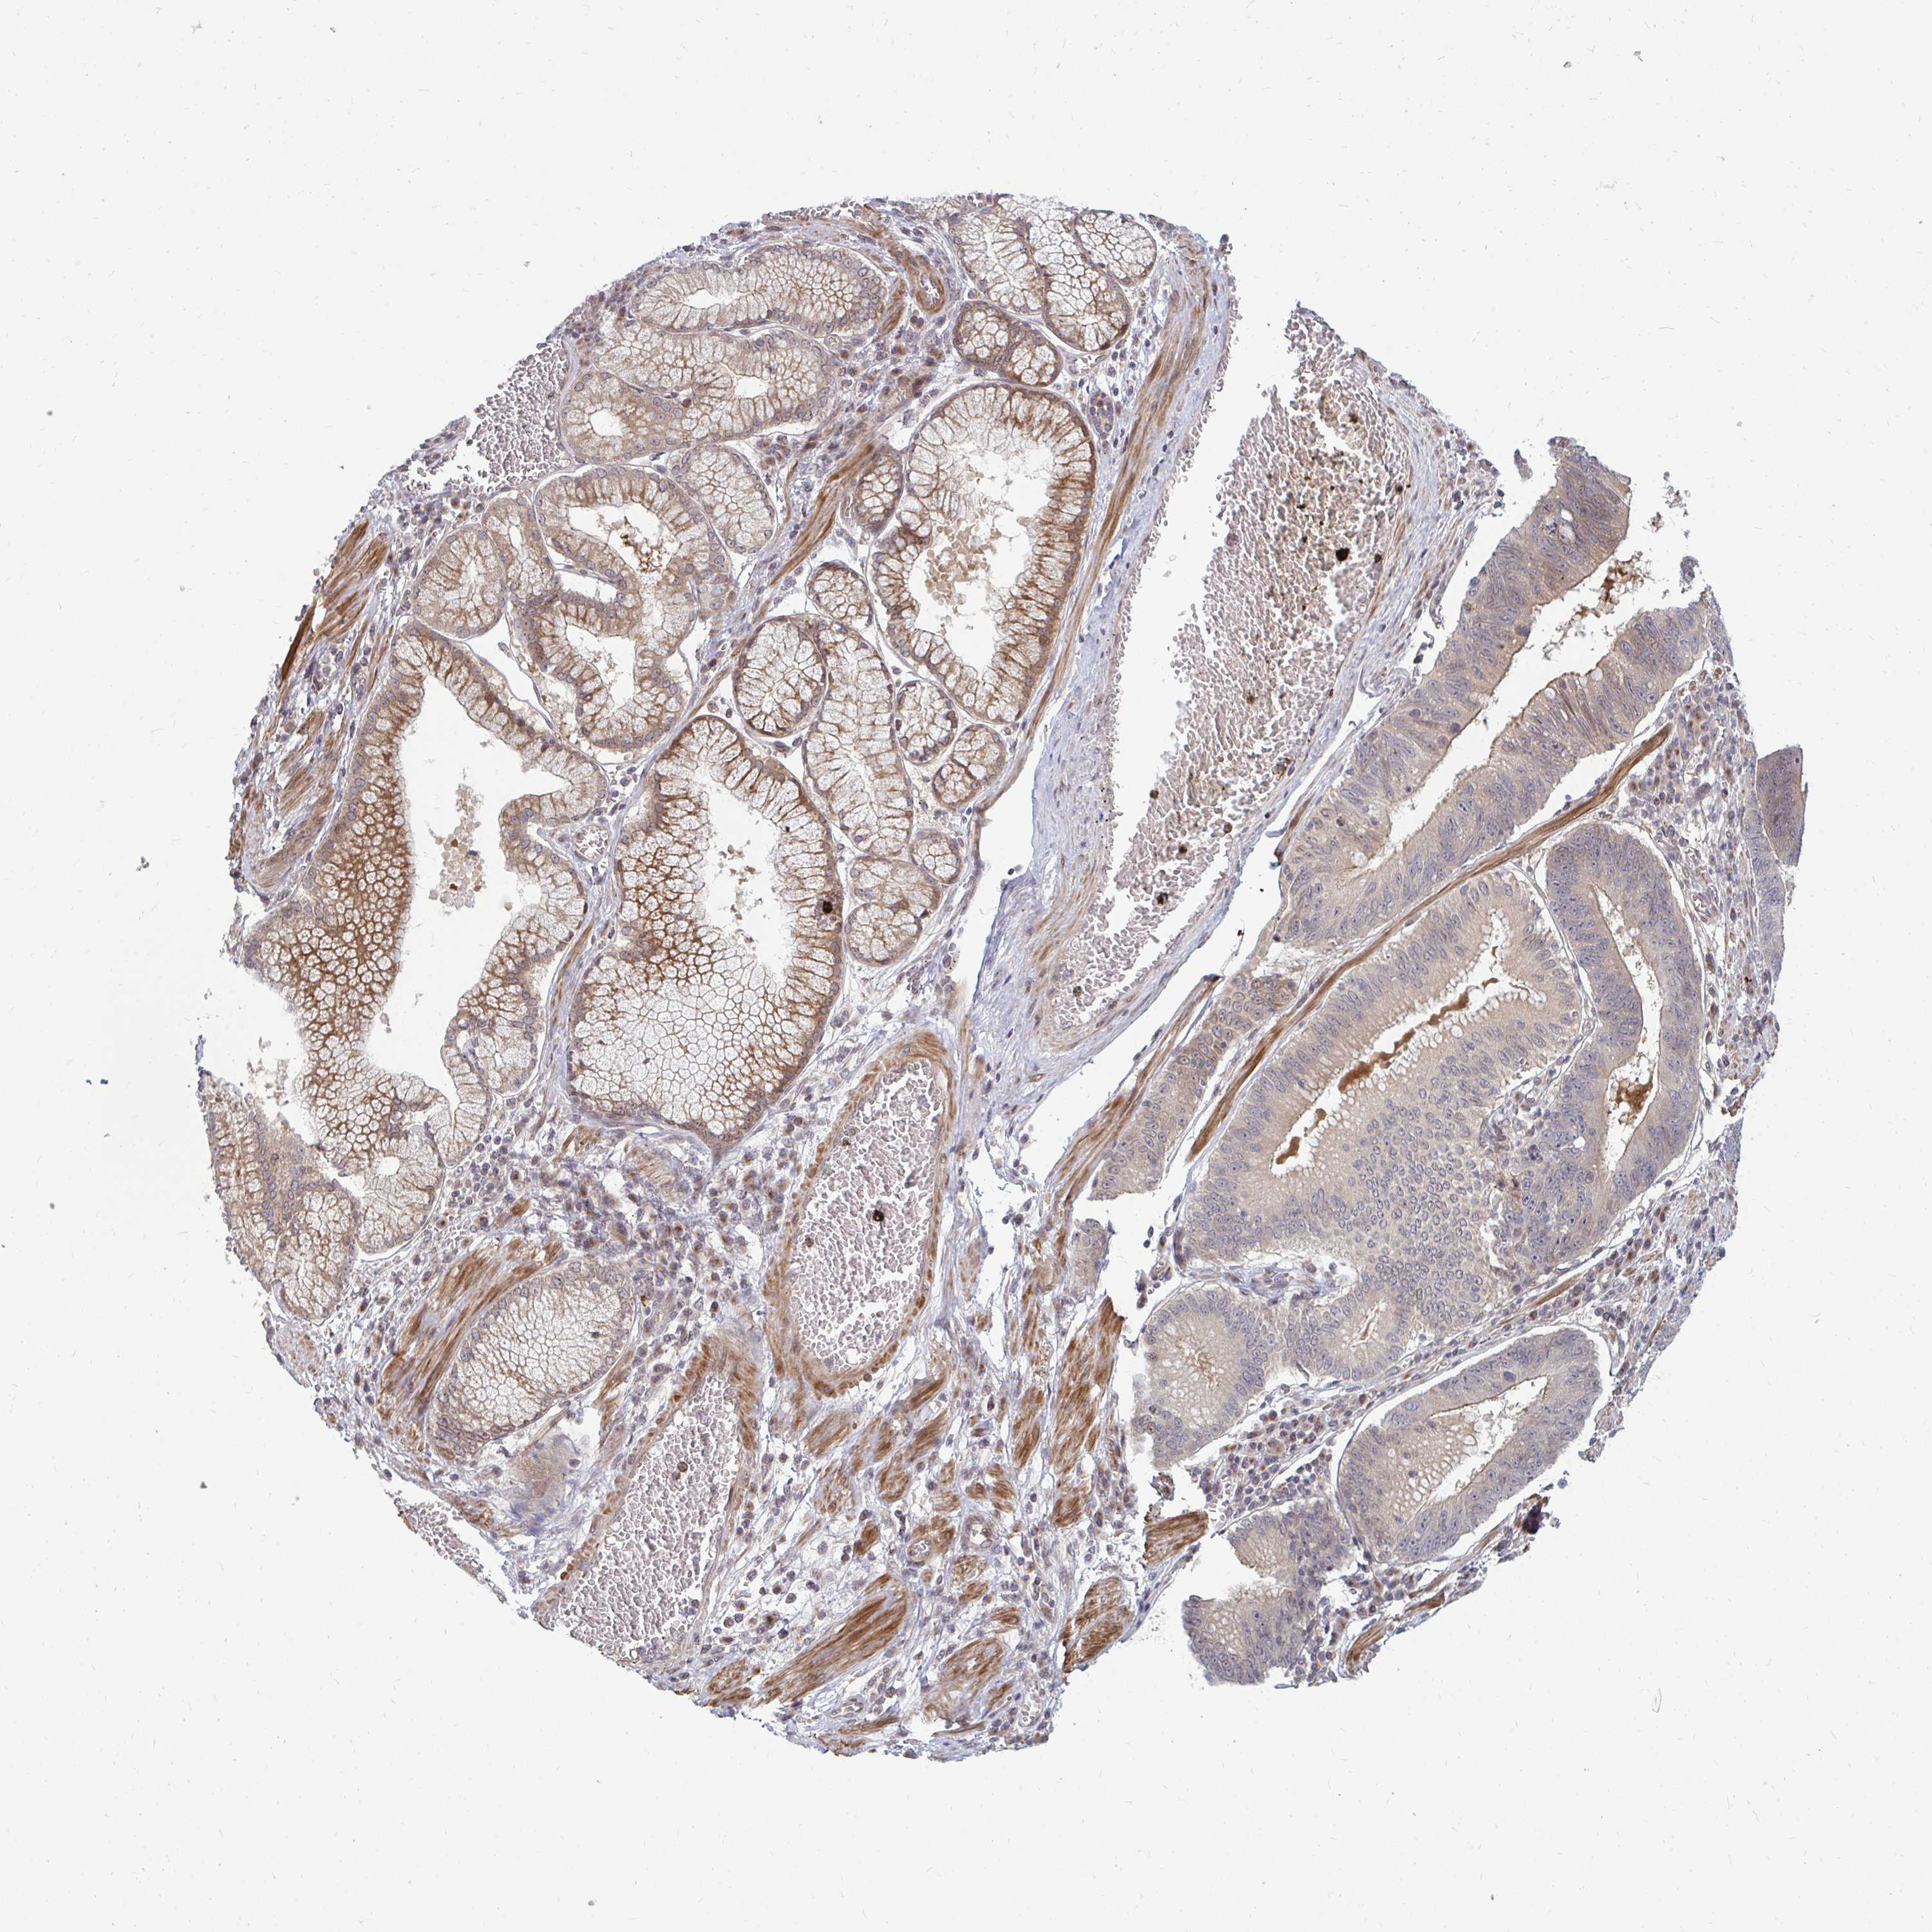

STOMACH CANCER - Protein expressioni

A mouse-over function shows sample information and annotation data. Click on an image to view it in a full screen mode. Samples can be filtered based on level of antibody staining by selecting one or several of the following categories: high, medium, low and not detected. The assay and annotation is described here.

Note that samples used for immunohistochemistry by the Human Protein Atlas do not correspond to samples in the TCGA dataset.

Antibody stainingi

Antibody staining in the annotated cell types in the current human tissue is reported as not detected, low, medium, or high, based on conventional immunohistochemistry profiling in selected tissues. This score is based on the combination of the staining intensity and fraction of stained cells.

Each image is clickable and will lead to virtual microscopy that enables deeper exploration of all samples and also displays staining intensity scores, fraction scores and subcellular localization as well as patient and tissue information for each sample.

Antibody HPA046100

Antibody HPA049212

Staining

High

Medium

Low

Not detected

Intensity

Strong

Moderate

Weak

Negative

Quantity

>75%

75%-25%

<25%

None

Location

Nuclear

Cytoplasmic/membranous

Cytoplasmic/membranous,nuclear

Adenocarcinoma, NOS